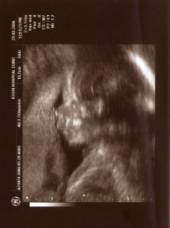

Lorsque

j’avais 21 semaines et que maman me sentait déjà bouger dans son ventre,

fin mars 2006, on a fait l’échographie du 2ème trimestre, dans

laquelle on peut voir :

mon

visage de profil,